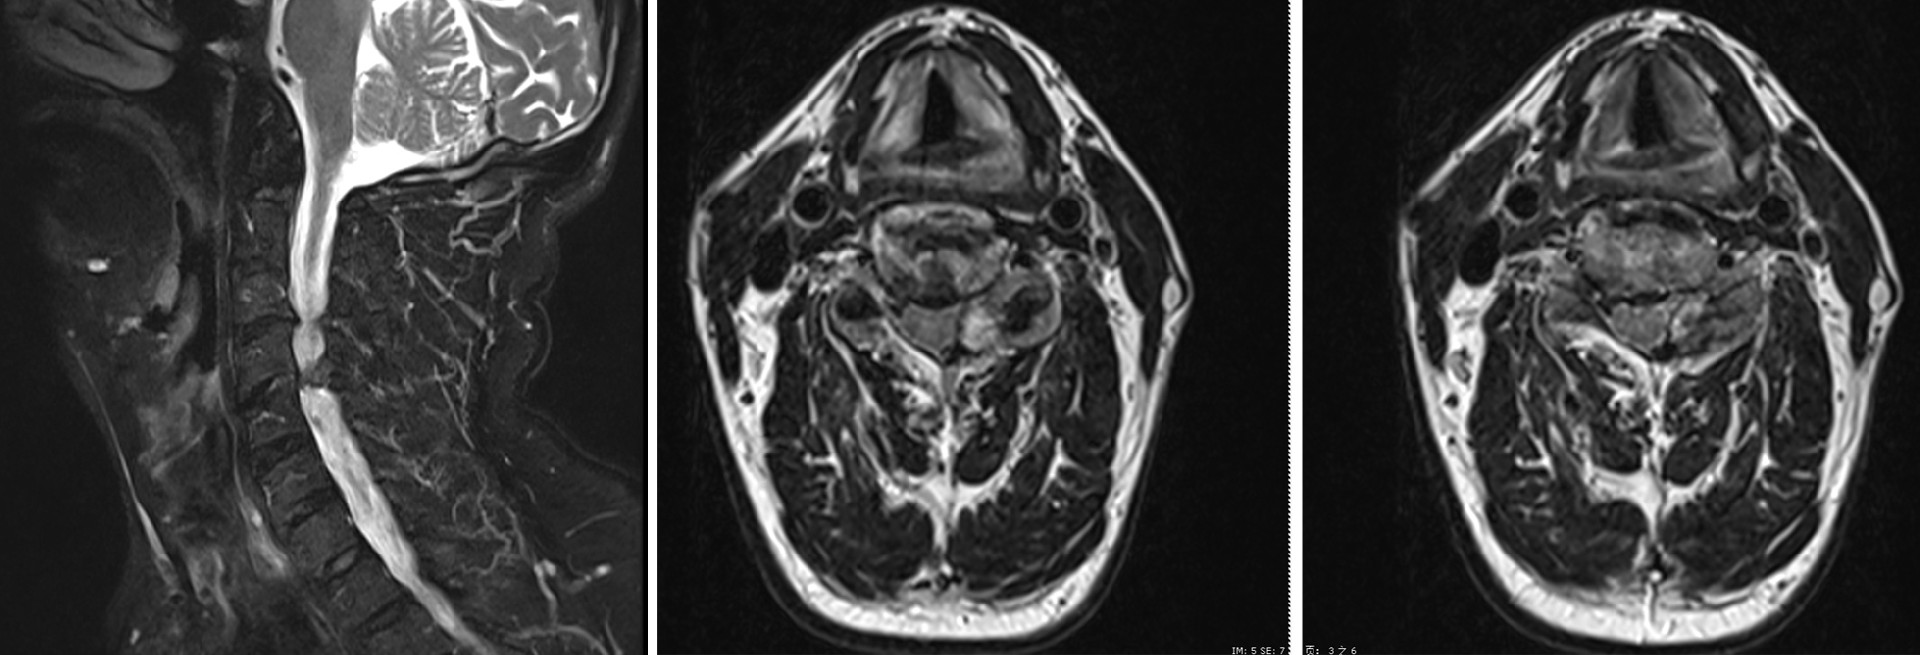

患者,男,61歲,頸肩疼痛及雙上肢麻木持續(xù)兩月余,并逐漸加劇,嚴(yán)重影響日常生活質(zhì)量,來我院就診。經(jīng)詳細(xì)門診檢查,特別是頸椎MRI精確診斷,明確患者的病因:C3/4水平椎管狹窄伴C4/5水平左側(cè)椎管內(nèi)占位性病變。

術(shù)前MRI圖像

患者病情比較復(fù)雜,朱中蛟副主任醫(yī)師、姜廣宗主治醫(yī)師及其診療團(tuán)隊(duì)?wèi){借豐富的臨床經(jīng)驗(yàn)和敏銳的洞察力,通過全面評估患者的CT和MRI影像資料,認(rèn)為患者的脊髓和神經(jīng)壓迫主要源自后方,且無明顯頸椎不穩(wěn)表現(xiàn),決定采用前沿的UBE技術(shù)進(jìn)行手術(shù)治療。